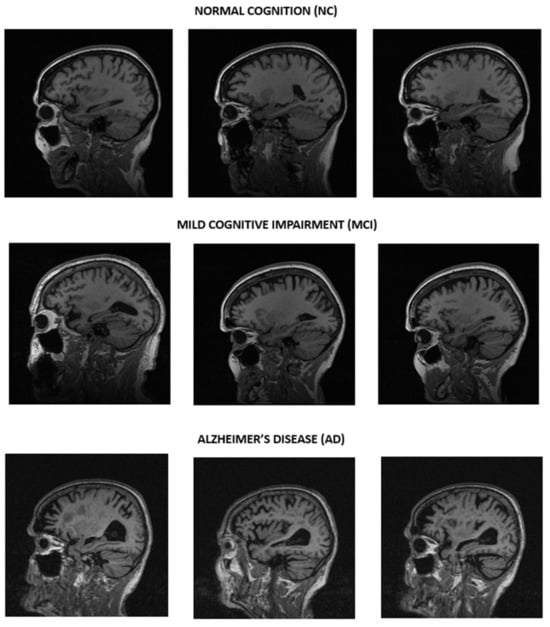

To conduct the experiments in this research, we used the Alzheimer’s Disease Neuroimaging Initiative (ADNI) data, which the Laboratory disseminated for Neuro Imaging at the University of Southern California. Samples can be seen in Figure 2.

This study is based on the publicly available, large-scale ADNI dataset consisting of 10,346 sagittal brain MRI scans, categorized into three classes, as shown in Table 1: normal cognition (NC), mild cognitive impairment (MCI), and Alzheimer’s disease (AD). Normal cognition is the label for patients that have no indicators of cognitive decline, such as no memory loss or motor impairments, as evidenced by the lack of pathological changes in their brain scans, while patients with mild cognitive impairment show signs of forgetfulness, which is consistent with signs of deterioration around the hippocampus. This progresses into moderate dementia, where patients begin to forget their personal history. When cognition continues to decline as the patient develops Alzheimer’s disease, more historical details are forgotten, along with confusion due to neuronal damage throughout the cerebral cortex, as evidenced by the narrowing of gyri coupled with the dilation of the sulci and ventricles. Severe dementia from this point requires supervision as patients begin to forget their family members while requiring assistance for daily activities due to the development of motor symptoms; this is the stage before death according to the global deterioration scale [2,3,4].

Figure 2. Raw MRI samples for normal cognition (NC) in the first row, mild cognitive impairment (MCI) in the middle row, and Alzheimer’s disease (AD) in the bottom row.